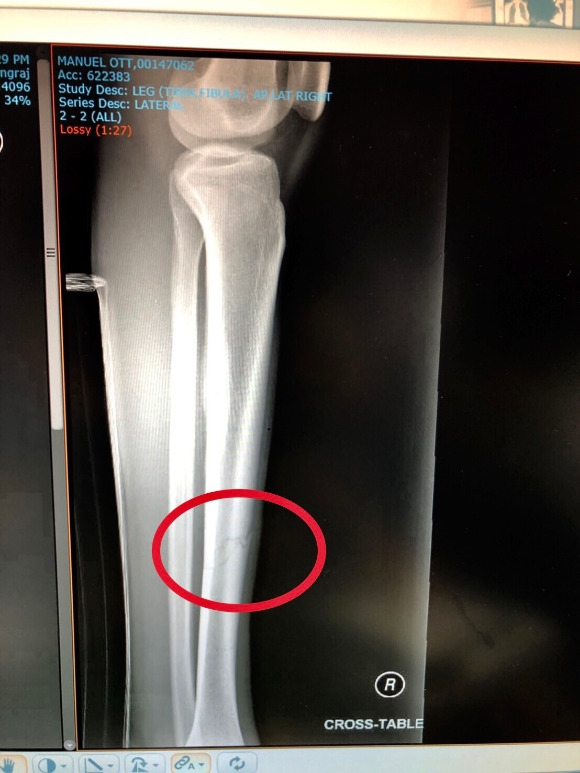

มานูเอล ออท นักเตะทีมชาติฟิลิปปินส์ของราชบุรี มิตรผล แข้งหักเตรียมเข้าผ่าตัดด่วนคาดพักยาวกว่า 3 เดือน

ข่าวร้ายของสโมสรราชบุรี มิตรผล เอฟซี ที่ต้องมาเสีย มานูเอล ออท กองกลางทีมชาติ ฟิลิปปินส์ ในช่วงปรีซีซั่น หลังประสบอุบัติเหตุในระหว่างซ้อม ปะทะบอลกับเพื่อนร่วมทีม จนกระดูกหน้าแข้งขวา แตก และหัก และเตรียมเข้ารับการผ่าตัดในวันที่ 11ก.พ.นี้ ซึ่งเบื้องต้นหลังจากตรวจอาการบาดเจ็บที่โรงพยาบาล ในจ.ราชบุรีคาดว่าน่าจะต้องพักรักษาอาการบาดเจ็บนานกว่า3เดือน ทำให้เลกแรกของไทยลีก2019 อาจจะไม่ได้ร่วมแข่งขัน แต่ทว่าอย่างไรก็ตามนักเตะและทีมงานยังเป็นกำลังใจให้กับ มานูเอล ออท และหวังว่าจะหาย กลับมาได้เร็วกว่าเวลาที่กำหนด